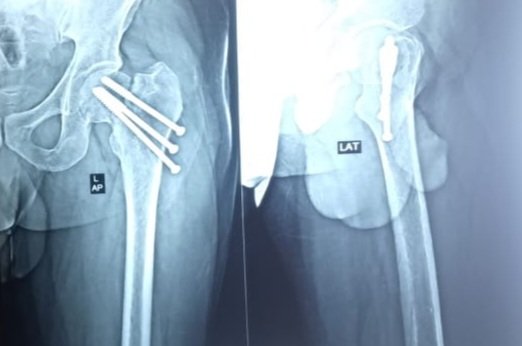

@traumaticum @ImprezowyKotek @orthobullets @orthotraumamd I see why a DHS… has the compression option that not all nails have, and it’s easier to add antirrotation or extra fixation screw in case needed. Also may let you correct valgus using the implant instead of forcing you to have it reduced before nail insertion. I like it.